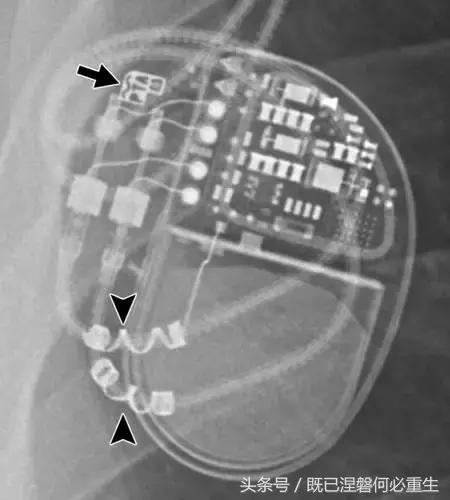

图。 9发生器引线断开。 移出的装置的放射线照片显示从末端完全退出的电极的外观(箭头)。 少数发电机没有容易识别的标志; 因此,制造商不能确定。

图10一名40岁女子的遗弃电极。 Medtronic发生器有两个端口(小箭头),但存在三个导联(一个心房和两个心室)。 对于传统的起搏器,有效导线的数量将等于或小于端口数量。 相对于端口的外部引线指示一个或多个引线被放弃。 因此,将端口数量与引线数量进行比较通常有助于识别丢弃的引线。 两个右心室导联之一以前发生故障,被放弃,而不是电极提取程序的风险并发症。 废弃的电极封盖(大箭头),以防止电气干扰。 未使用的端子也加盖并堵塞。